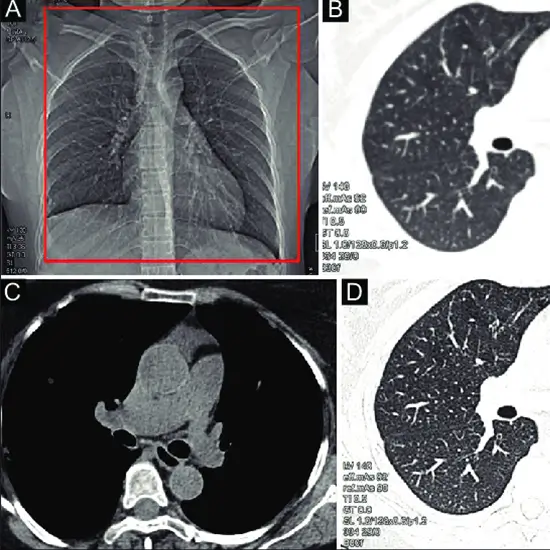

The forearm (including the wrist, radius, ulna, and elbow) and upper arm can be visualised using non-contrast computed tomography (NCCT) (between shoulder and elbow). It is performed to determine the source of arm pain, tenderness, swelling, and deformity. It aids in the detection of bone alignment, fracture, tumour, degeneration, and other bone-related issues in the arm.

This test is used to detect fractures in the bones of the arm that are not visible on a standard X-ray. • To diagnose any suspected infection, osteoporosis, deformities or abnormal bone growth, and arthritis; and • To detect any infection, injury, or inflammation of the soft tissues such as the muscle, tendons, and ligaments of the arm (inflammation of the joints)